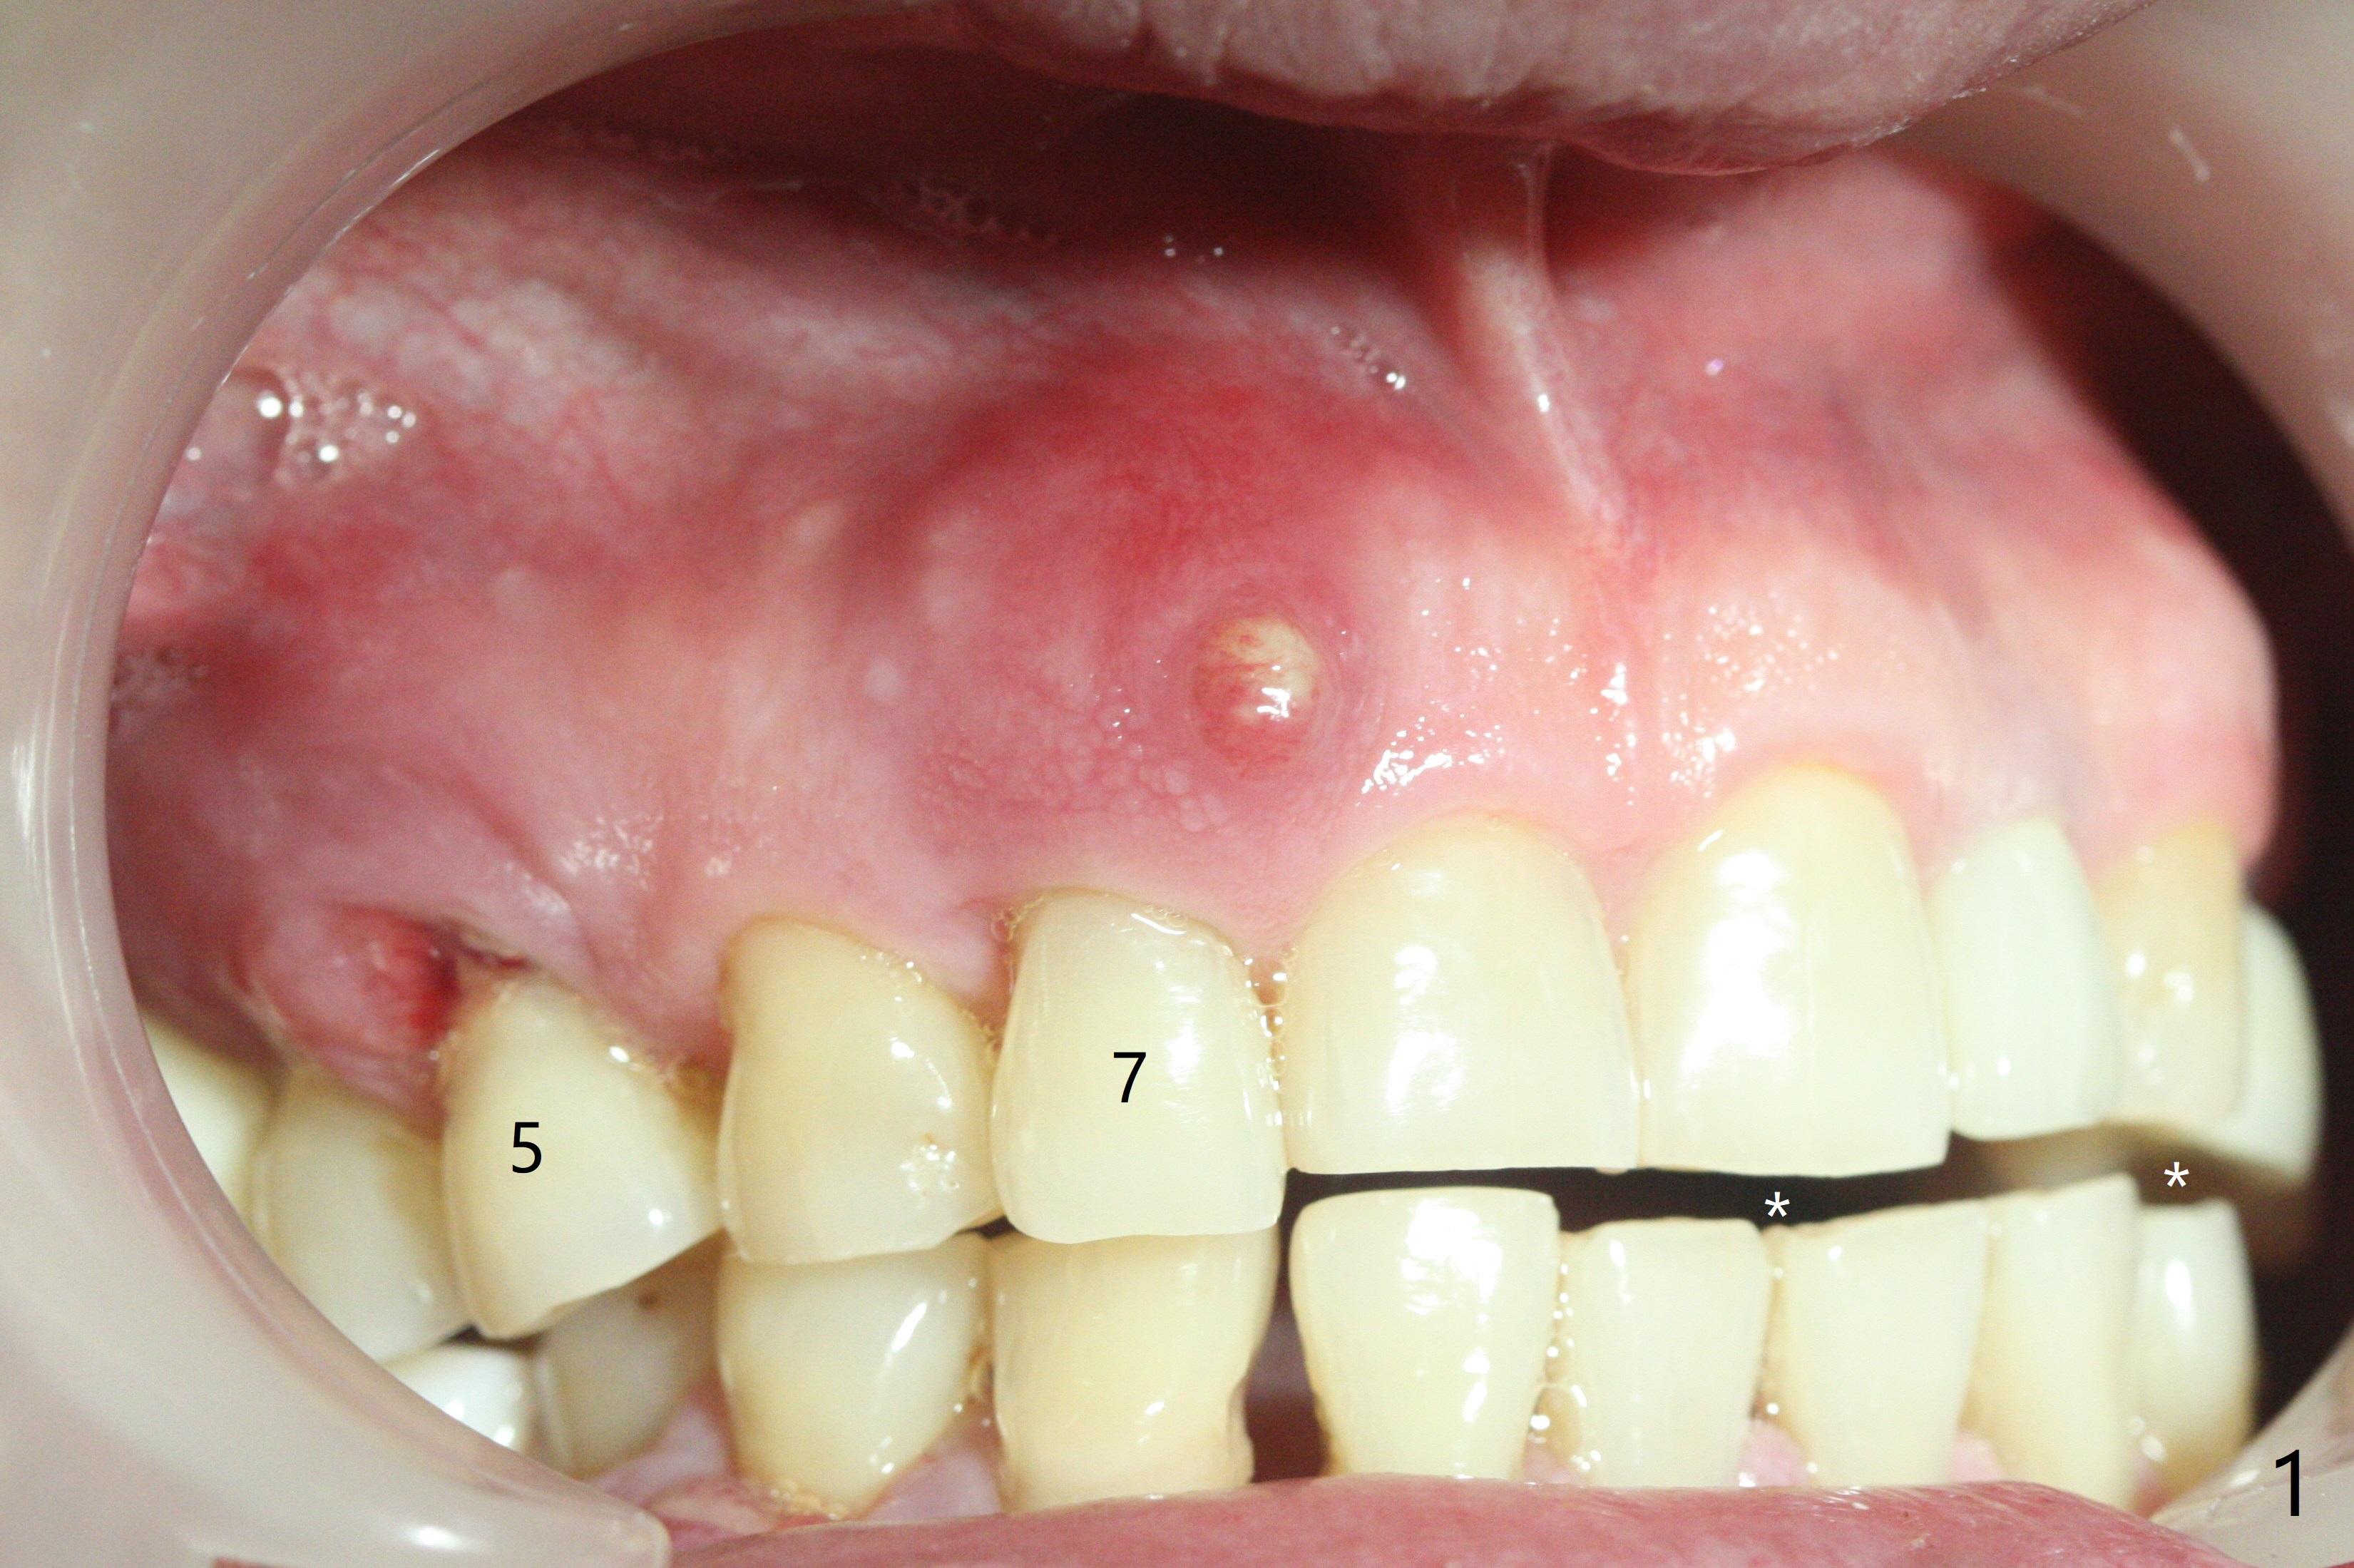

A 67-year-old man returns for periodic exam and #19 impression (Fig.3), which is impossible because there is open bite on the left (Fig.1 *). The latter is related to several periodontal abscesses (supraeruption, Fig.1,2). His chief complaint is mobility of #31 (Fig.3,4). Due to severity of infection, #31 is extracted with bone graft retained by Titanium-Reinforced Membrane (Cytoplast, Fig.5 T). PTFE suture is used. It is easy to tie knots with this non-resorbable (absorbable) suture. The Titanium-Reinforced Membrane exposes 1.5 months postop (Fig.6), which makes its removal easy (Fig.7). In fact the patient is pre-diabetic.